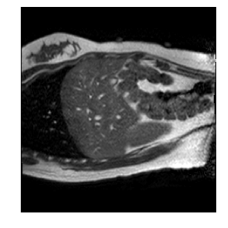

With this motivation, [6] proposed a convolutional neural network (CNN) based approach for temporal interpolation of navigators. Their CNN takes as inputs a fixed number of acquired images and learns to predict the missing images directly in the intensity space. This approach, which we call the Simple Convolutional Interpolation Network (SCIN), is a ’black-box’ formulation that does not incorporate any prior information about the interpolation process. Image prediction is guided only by the cost function used to optimize the network parameters. The issue with this is that it is unclear whether the image similarity measures that are generally used as cost functions suffice to ensure fidelity of the generated images to the original images. Indeed, Fig. 1b shows a case where an image interpolated using SCIN is quite blurry and misses several liver and lung structures present in the original image.

Figure 1: (a) Ground truth and (b,c) interpolated images from (b) baseline (SCIN) and (c) proposed method (MFIN). The image interpolated via SCIN is heavily blurred and misses several lung and liver structures, while the proposed method is able to preserve the details in the ground truth image.